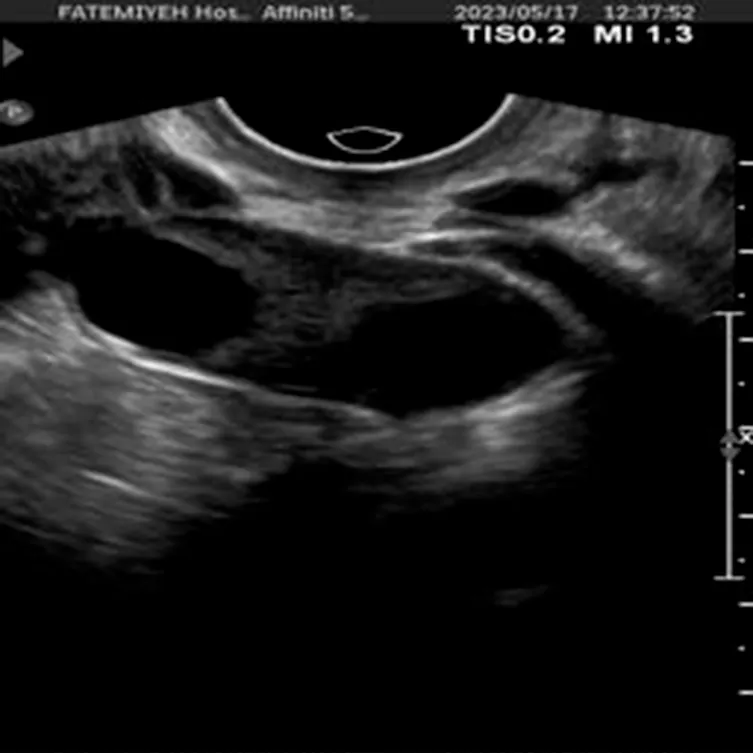

The dataset used in this study was collected from Fatemieh Hospital of Hamedan University of Medical Science during the years 2023 and 2024. It consists of ultrasound images, each with a resolution of 1,024 × 1,024 pixels, capturing various ovarian conditions. The dataset is organized into three distinct classes: Normal, Dominant Follicle, and Polycystic Ovary Syndrome (PCO). These classes represent crucial clinical states requiring different management approaches, with Normal indicating healthy ovarian function, Dominant Follicle associated with ovulatory cycles, and PCOS characterized by the presence of multiple small cysts, a key feature of polycystic ovary syndrome.

To provide further context, the dataset consists of 301 transvaginal ultrasound images, each corresponding to a unique patient, resulting in a total of 301 women aged between 20 and 45 years. All ultrasound scans were performed using a Philips Affiniti 50 system (Philips, Netherlands). To ensure consistency and clinical accuracy, all images were captured by a single board-certified obstetrician-gynecologist with fellowship training in infertility.

The dataset includes a total of 301 labeled ultrasound images, as shown in Table 1, with 41 images classified as Normal, 144 as Dominant Follicle, and 116 as PCO. The labeling was performed by experienced radiologists, ensuring high-quality ground truth for model training and evaluation.

Additionally, Figure 1 below presents a sample of ultrasound images from each of the three classes, demonstrating the visual differences between the conditions and the challenges involved in classification.

Figure 1

www.frontiersin.org

Figure 1. Sample ultrasound images from the dataset, representing the three classes: (a) Normal, (b) Dominant Follicle, and (c) Polycystic Ovary Syndrome (PCO). These examples highlight the visual differences between the classes used for muticlass classification.